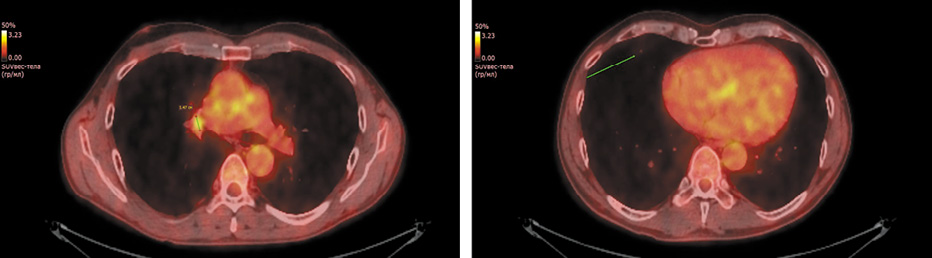

Рис. 3. Пациент 2. Позитронно-эмиссионная компьютерная томография органов грудной клетки от 23.06.2021 г. Снижение метаболической активности метастаза в лимфатический узел средостения, регресс опухоли легкого.

Fig. 3. Patient 2. Chest positron emission computed tomography,23.06.2021. The reduction of metabolic activity in mediastinal lymph node metastases, lung tumor regression.